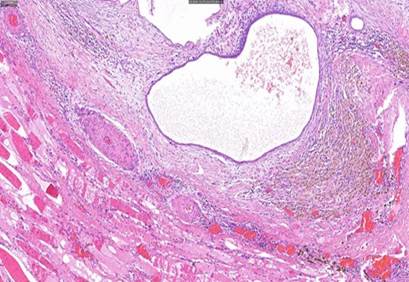

Respecto al caso 1, tras el análisis de la lesión, la descripción macroscópica coincide con un nódulo de tejido adiposo de 2 cm x 2cm que presenta áreas blanquecinas y otras rojizas al corte. Mientras que microscópicamente se describe como tejido fibroadiposo que incluye algunos fascículos nerviosos y estructuras vasculares, con numerosos focos de mucosa endometrial con glándulas focalmente dilatadas rodeadas por estroma celular y compacto. El diagnóstico final fue endometriosis subcutánea en relación con cicatriz de cesárea. Respecto a los resultados macroscópicos y microscópicos de los casos 2, 3 y 4, la conclusión respecto a su análisis acaba siendo, en todos los casos, lesiones nodulares de consistencia firme, de tamaños 2,5 cm x 2 cm; 6 cm x 6 cm, y 4 cm x 4 cm, respectivamente; con diagnóstico final de endometriosis cutánea, encontrándose tejido y estroma endometrial y glándulas, además de tejido hemorrágico, fibroso y adiposo (Figuras 3, 4, 5).

Figura 5 HE 10x. Tejido de músculo estriado (esquina inferior izquierda) próximo a glándulas endometriales dilatadas con material hemático en su interior (centro) y a histiocitos con hemosiderina (margen derecho).